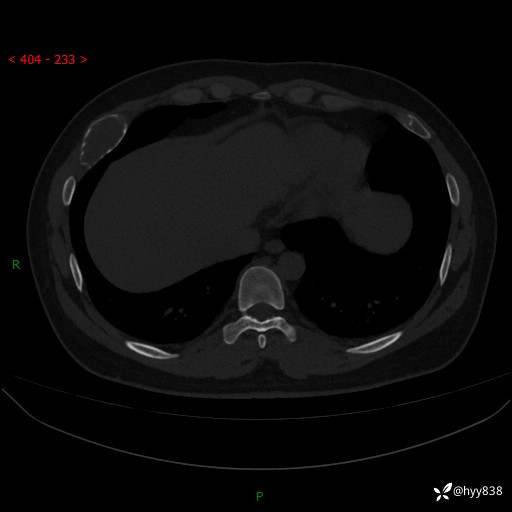

年轻小伙,右侧胸部疼痛4天余。病理科说肯定不是骨纤,那是啥---结果公布~

年龄:24岁

主诉:右侧胸部疼痛4天余。

现病史:患者约4天前突发右侧胸部疼痛,无瘙痒,无头痛、头晕,无心慌、胸闷、呼吸困难、咳嗽、咳痰、咯血,无腹痛、腹胀等不适,未作进一步诊治。于2024年5月外院行胸部CT平扫示右侧肋骨骨质改变。现为求进一步治疗,遂于我院就诊。门诊以“胸壁肿物”收入我科。 患者自起病以来,精神可,睡眠可,饮食可,大小便正常,体重无明显改变。

胸部CT平扫